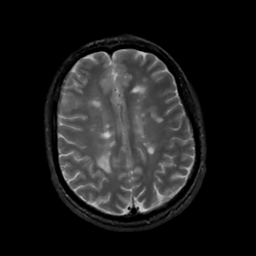

MR Study #5, March 10, 1991 -- Slice #35

[Home][Help][Clinical][Tour 1][Tour 2] Slice 35